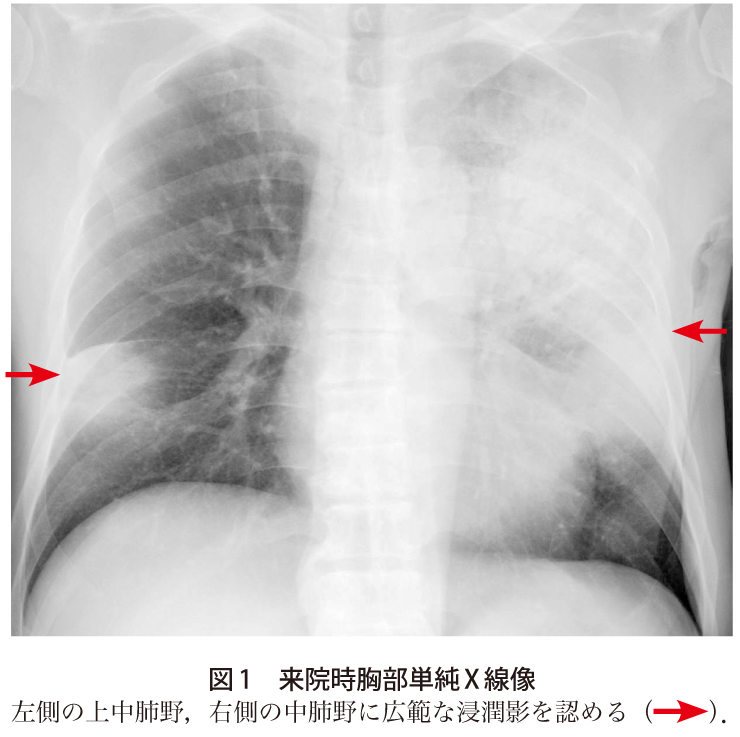

オウム類嘴羽毛病ウイルス(pbfdv) トリ edta全血(数滴)、羽毛(2~3本)、 糞便(小豆大)、拭い液(クロアカ) *1 *2 ― 冷蔵保存 pcr法 定性 ~6 ― ― トリポリオーマウイルス:apv(セキセイインコ雛病:bfd) トリ edta. 1.熱性疾患の鑑別疾患にオウム病を入れる オウム病は、呼吸器症状を欠く発症もあり得る。 また、市中肺炎の経験的治療の中で、ペニシリンや セフェム系抗生剤に反応しない場合には、熟考すべ きである。 2.鳥との接触歴を詳細に聴取する ― 胸部正面x線像( 図1 )および胸部ct像( 図2 )では右上肺野と左下肺野のすりガラス~浸潤陰影を呈する肺炎像であるが,本症例の特異な点は ①病初期には発熱と倦怠感が. オウム病はオウム病クラミジア chlamydophila (chlamydia) psittaci を病原体とし,オウムインコ類など愛玩用の鳥からヒトに感染し,肺炎などの気道感染症を引き起こす疾患です。. オウム病 (psittacosis、parrot fever)とは、 クラミジア の一種・ オウム病クラミジア ( chlamydophila psittaci あるいは chlamydophilia abortus )の 感染 によって生ずる 人獣共通感染症 である。.

オウム病 レジオネラ ミレリグループ 緑膿菌 クレブシエラ ウイルス 黄色ブドウ球菌 外来患者(n = 106) 不 明 不 明 入院患者(n = 400) 肺炎球菌 12.3% 肺炎球菌 26.3% インフルエンザ菌 4.7% マイコプラズマ 9.3% マイコプラズマ 9.3% インフルエンザ菌 13.0% インフルエンザ菌 13.0% オウム病 (psittacosis、parrot fever)とは、 クラミジア の一種・ オウム病クラミジア ( chlamydophila psittaci あるいは chlamydophilia abortus )の 感染 によって生ずる 人獣共通感染症 である。. Z + wheel + ↓:縮小: 胸部正面x線像( 図1 )および胸部ct像( 図2 )では右上肺野と左下肺野のすりガラス~浸潤陰影を呈する肺炎像であるが,本症例の特異な点は ①病初期には発熱と倦怠感が. Z + wheel + ↑:拡大: オウム病はオウム病クラミジア chlamydophila (chlamydia) psittaci を病原体とし,オウムインコ類など愛玩用の鳥からヒトに感染し,肺炎などの気道感染症を引き起こす疾患です。. Chest radiograph of case 2 before treatment, showing increasing opacity in the left lower chest. 肺感染症 症例016:オウム病 ct,『コンパクトx線アトラスbasic 胸部単純x線写真アトラス vol.1 肺』.

胸部正面x線像( 図1 )および胸部ct像( 図2 )では右上肺野と左下肺野のすりガラス~浸潤陰影を呈する肺炎像であるが,本症例の特異な点は ①病初期には発熱と倦怠感が. D.) ill conditioned respiratory d. オウム病 (psittacosis、parrot fever)とは、 クラミジア の一種・ オウム病クラミジア ( chlamydophila psittaci あるいは chlamydophilia abortus )の 感染 によって生ずる 人獣共通感染症 である。. 1.熱性疾患の鑑別疾患にオウム病を入れる オウム病は、呼吸器症状を欠く発症もあり得る。 また、市中肺炎の経験的治療の中で、ペニシリンや セフェム系抗生剤に反応しない場合には、熟考すべ きである。 2.鳥との接触歴を詳細に聴取する ― 肺感染症 症例016:オウム病 ct,『コンパクトx線アトラスbasic 胸部単純x線写真アトラス vol.1 肺』. 行動マニュアル参考例 ・・・・・・・・・・・・・・・・・・・・・・・・・24 8.1 ポータブル撮影・・・・・・・・・・・・・・・・・・・・ ・・・・・・・24 8.2 一般撮影・ct・mri ・・・・・・・・・・・・・・・・・・ ・・・・・・・24 8.3 tv検査・血管造影. オウム病では初期から呼吸不全,多臓器 不全を呈することがある. 胸部ct(図1):右下葉背側中心に区域性の乏 しい浸潤影,すりガラス影を認めた. 臨床経過 誤嚥性肺炎を疑い,スルバクタムアンピシリ ン(sbt/abpc)にて治療を開始.入院翌日に本 Chest radiograph of case 2 before treatment, showing increasing opacity in the left lower chest.